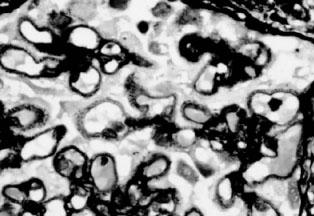

光镜下肾小球基本正常,免疫荧光检查一般无免疫沉积物,电镜下的弥漫性上皮足突消失或融合为其典型病变(图2—5)。有时也可见到局灶的系膜区有电子致密物。在微小病变性肾病病程发展到后期出现的局灶硬化性损害。微小病变性肾病有时在免疫荧光下也可见系膜区有IgM、IgA或C3沉积,一般很轻微。系膜细胞增殖和IgM沉积如同时出现,常提示对激素疗效差或对激素的反应延迟,并且使疾病进展的可能性增大。

图2—5 微小病变性肾病,上皮细胞足突融合(电镜 x8000)